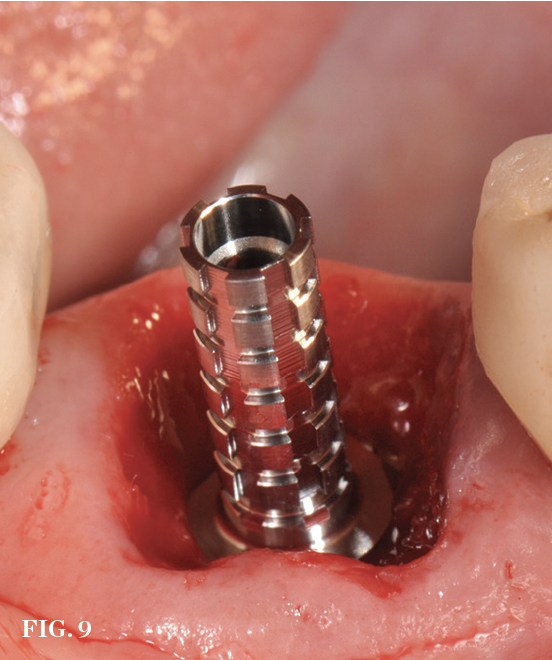

(9.) Chairside custom healing abutment fabrication in progress using a temporary abutment.

Figure 9

In the molar region, the preparation of sites with large septa presents its own challenges, especially when carried out in an analog fashion. Fully guided preparation of the osteotomy and implant placement reduces the potential for the drill to drift or the implant to migrate into the adjacent socket defects (Figure 5 through Figure 9).